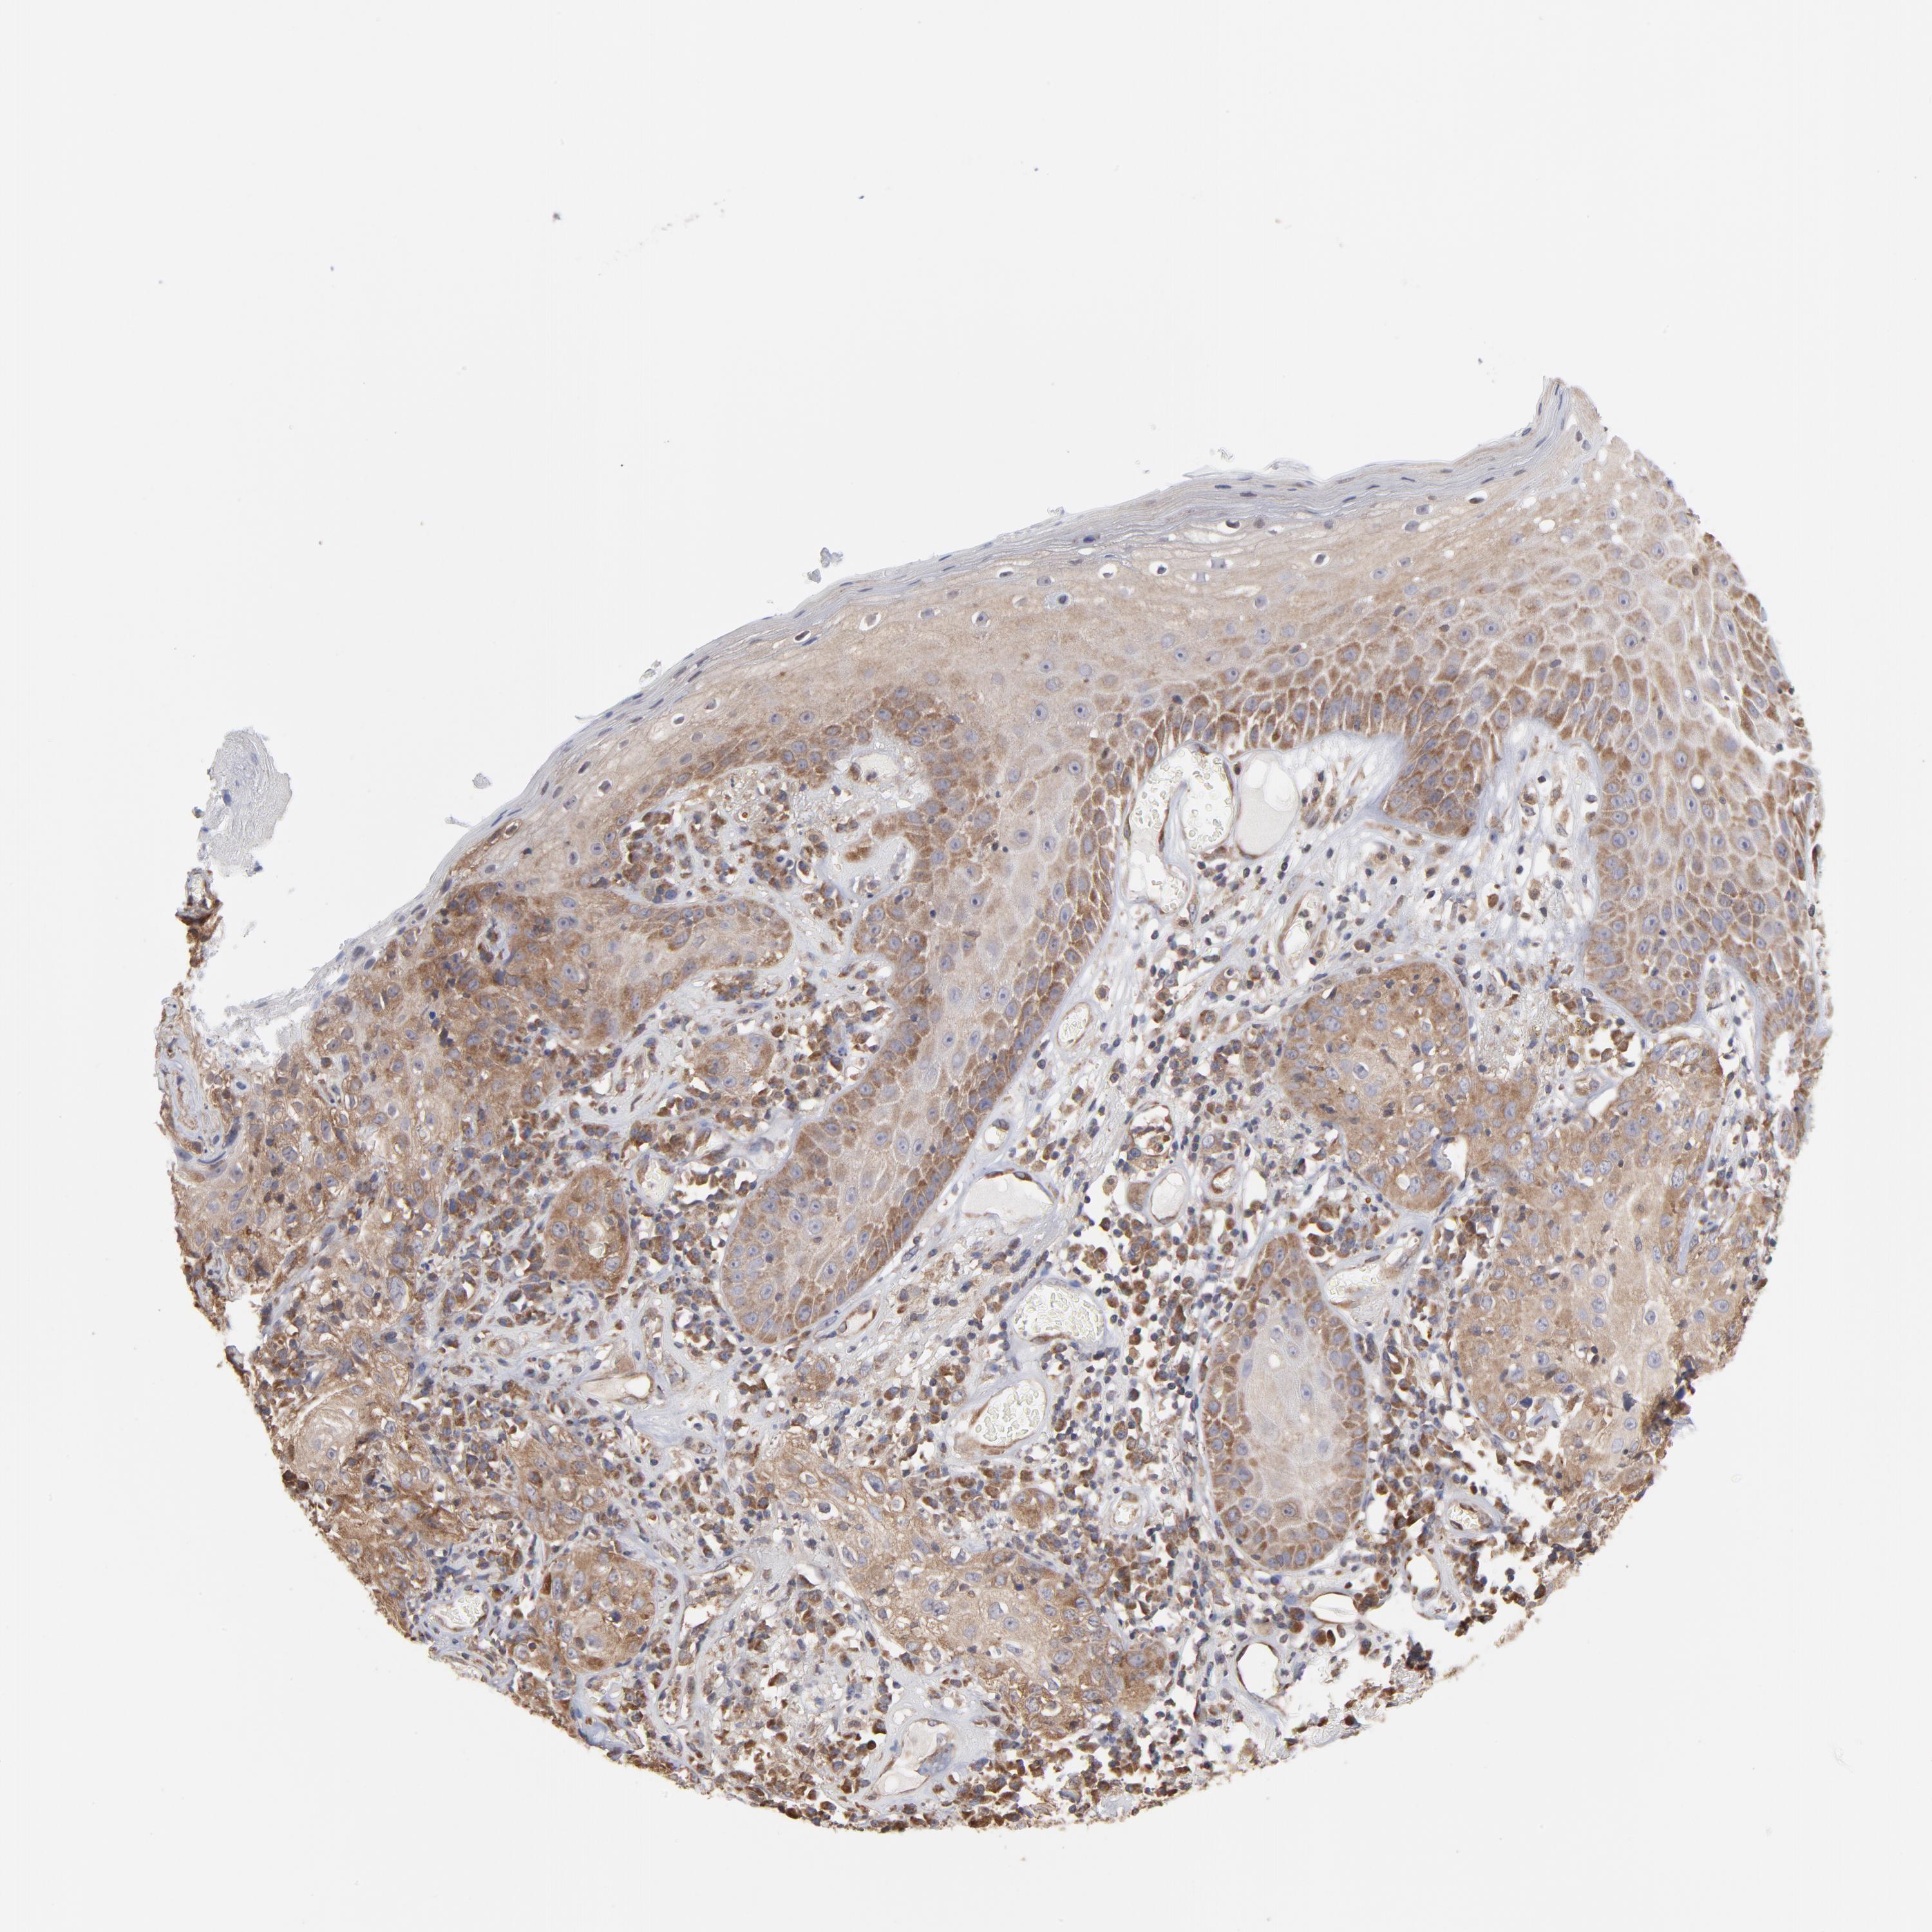

Basal cell and squamous cell cancer

SKIN CANCER - Protein expressioni

A mouse-over function shows sample information and annotation data. Click on an image to view it in a full screen mode. Samples can be filtered based on level of antibody staining by selecting one or several of the following categories: high, medium, low and not detected. The assay and annotation is described here.

Antibody stainingi

Antibody staining in the annotated cell types in the current human tissue is reported as not detected, low, medium, or high, based on conventional immunohistochemistry profiling in selected tissues. This score is based on the combination of the staining intensity and fraction of stained cells.

Each image is clickable and will lead to virtual microscopy that enables deeper exploration of all samples and also displays staining intensity scores, fraction scores and subcellular localization as well as patient and tissue information for each sample.

Antibody CAB009337

Staining

Intensity

Quantity

Location

Basal cell carcinoma